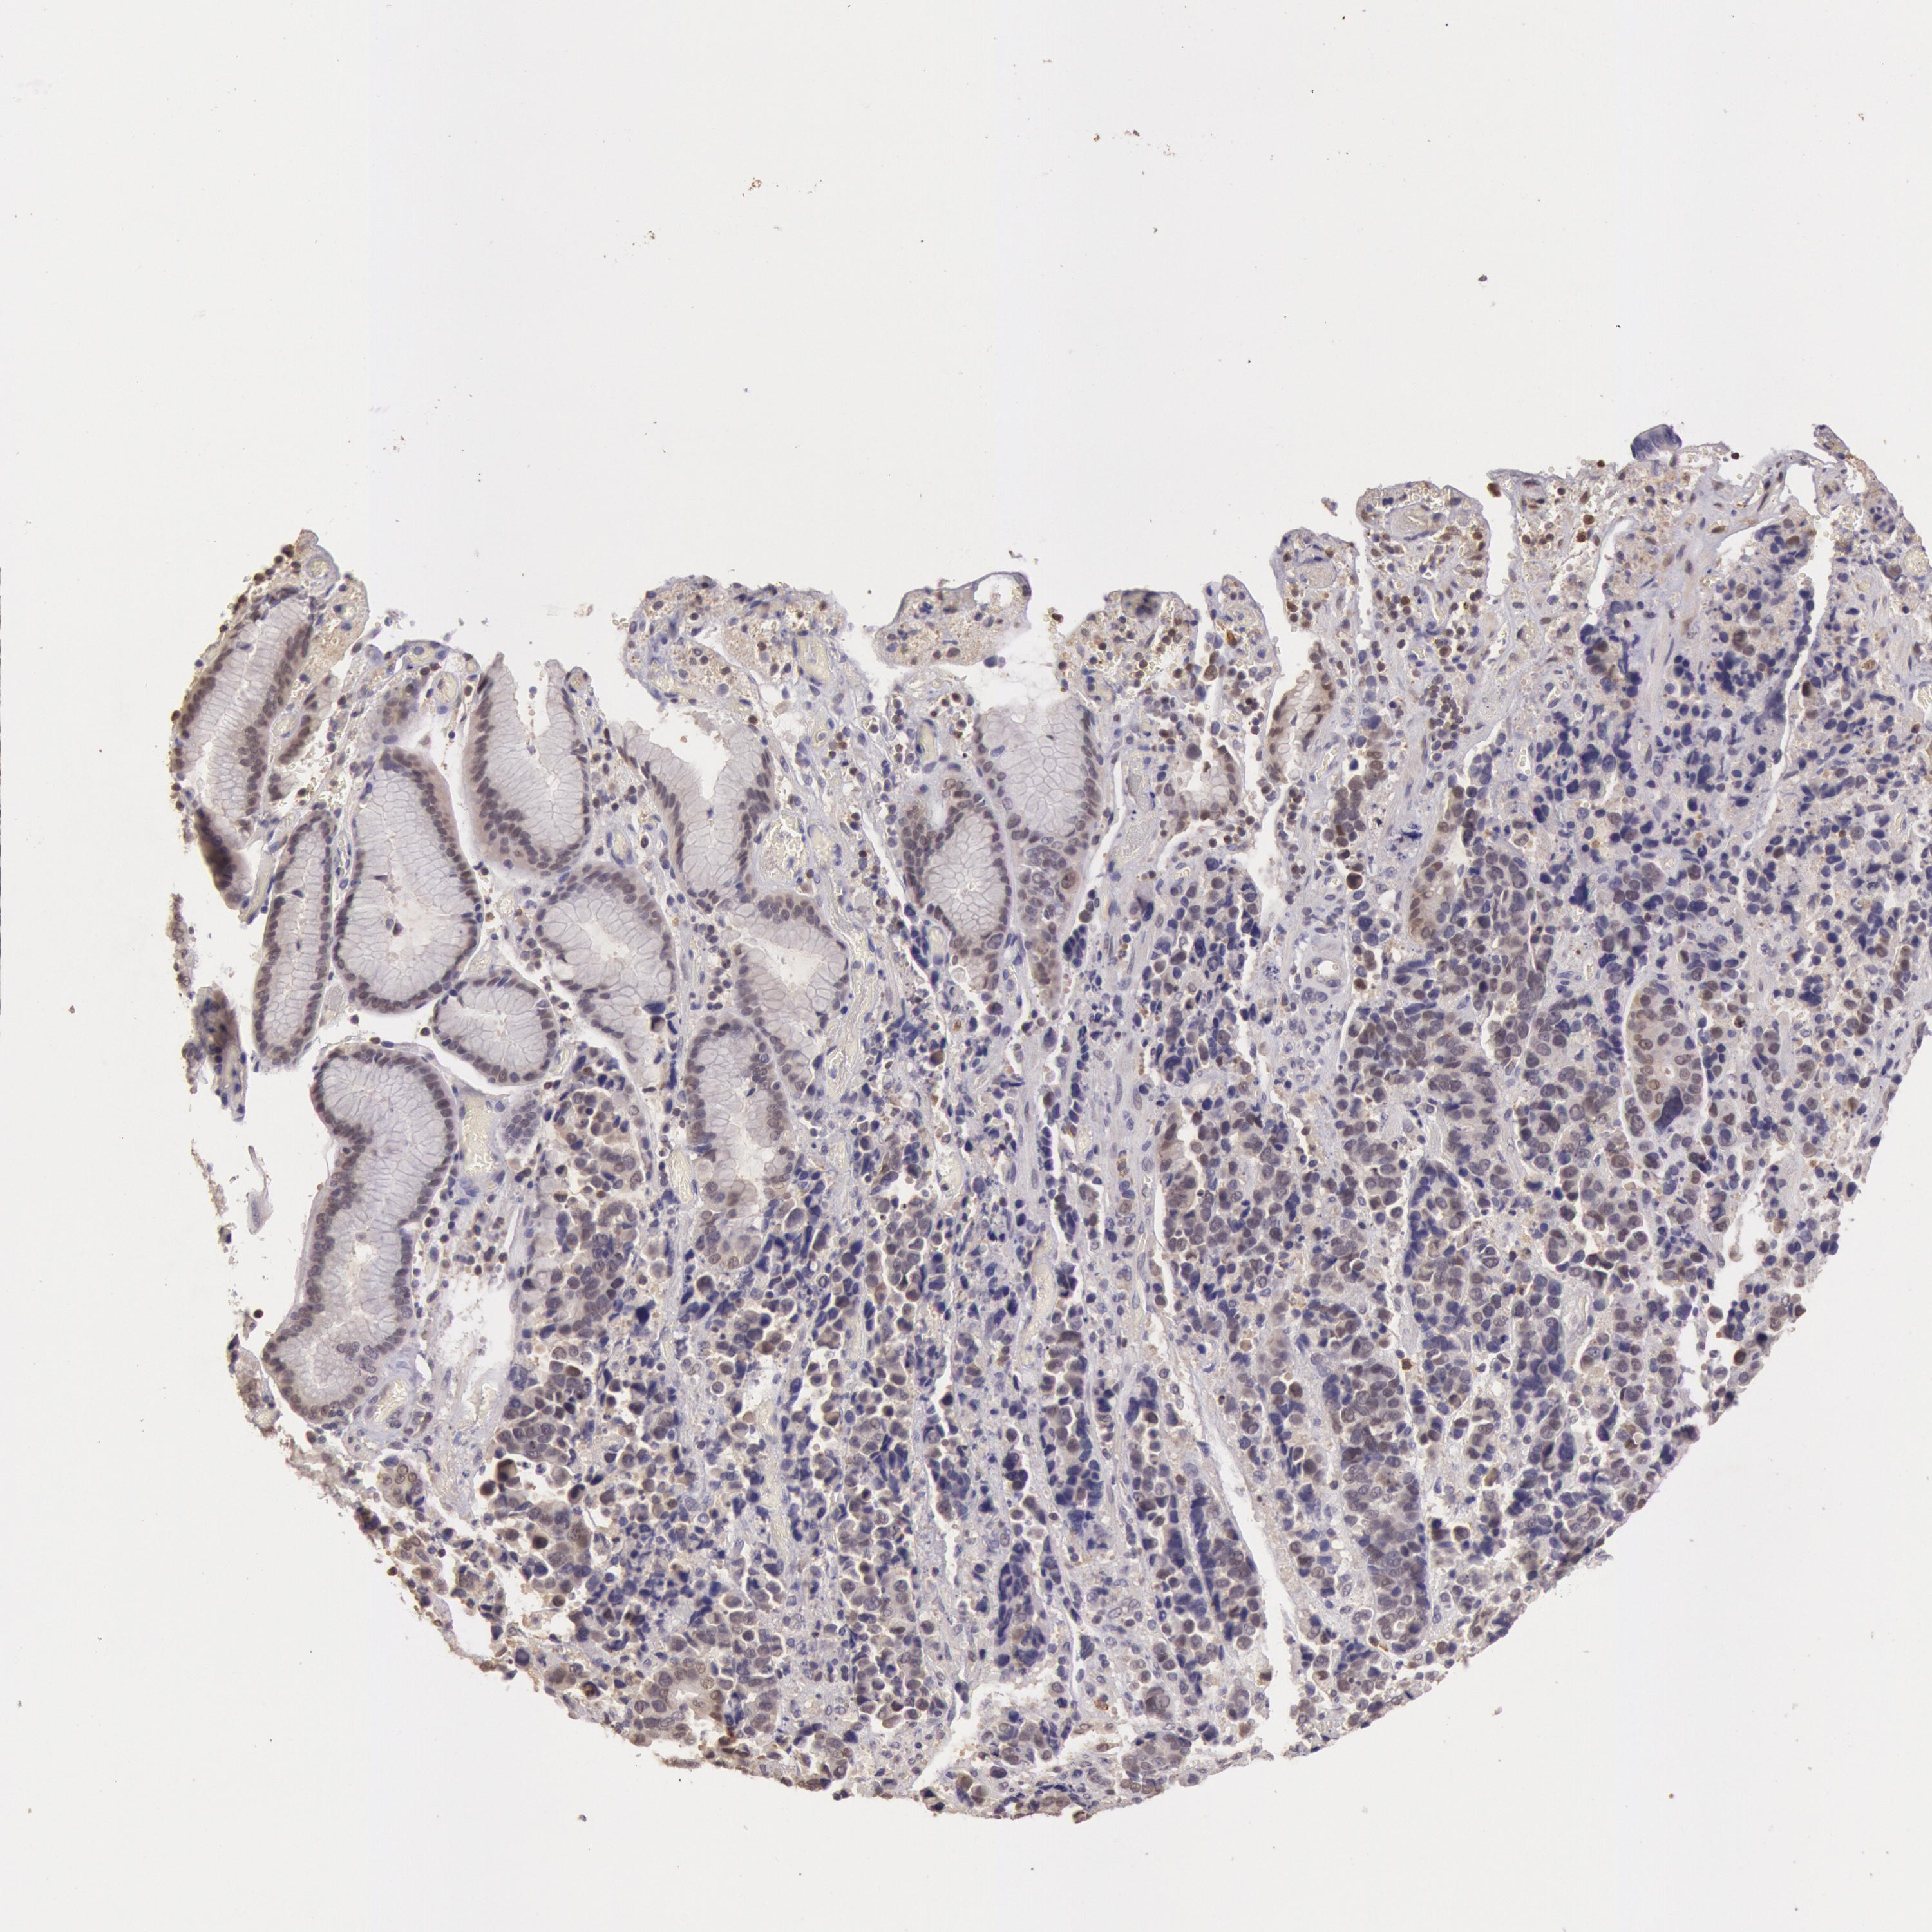

STOMACH CANCER - Protein expressioni

A mouse-over function shows sample information and annotation data. Click on an image to view it in a full screen mode. Samples can be filtered based on level of antibody staining by selecting one or several of the following categories: high, medium, low and not detected. The assay and annotation is described here.

Antibody stainingi

Antibody staining in the annotated cell types in the current human tissue is reported as not detected, low, medium, or high, based on conventional immunohistochemistry profiling in selected tissues. This score is based on the combination of the staining intensity and fraction of stained cells.

Each image is clickable and will lead to virtual microscopy that enables deeper exploration of all samples and also displays staining intensity scores, fraction scores and subcellular localization as well as patient and tissue information for each sample.

Antibody HPA001401

Antibody CAB008670

Staining

High

Medium

Low

Not detected

Intensity

Strong

Moderate

Weak

Negative

Quantity

>75%

75%-25%

<25%

None

Location

Nuclear

Cytoplasmic/membranous

Cytoplasmic/membranous,nuclear

Adenocarcinoma, NOS